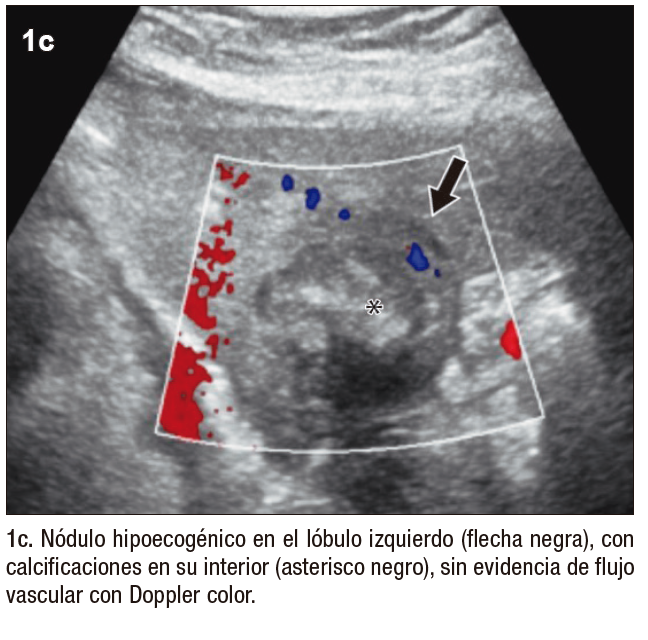

Posteriormente, se realiza una ecografía abdominal en la que se muestran innumerables nódulos hipoecogénicos, de márgenes parcialmente circunscritos, con calcificaciones en su interior, algunos causantes de retracción capsular, sin evidencia de flujo vascular con Doppler color (Figura 1). Tras estos hallazgos, se continúa la valoración mediante TCMD (Tomografía Computada Multi detector) con contraste endovenoso, donde se observan, en consonancia con la ecografía, numerosos nódulos isodensos e hipodensos, con realce en anillo en fases arterial y venosa, distribuidos en ambos lóbulos hepáticos.

Figura 1. Ecografía hepática con transductor convexo, en modo B (a y b) y Doppler color (c)

Figura 1. Doppler color (c)